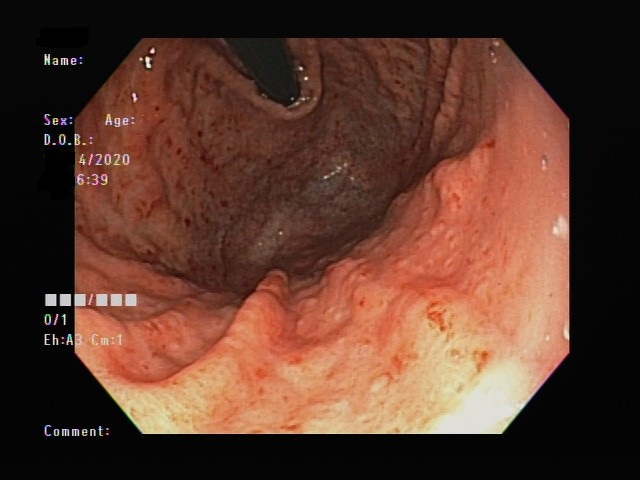

可以,有些胃潰瘍、幽門桿菌感染是沒有症狀的。像下面圖片的患者,就完全沒有腹部不適,卻明顯有胃發炎合併幽門桿菌感染。